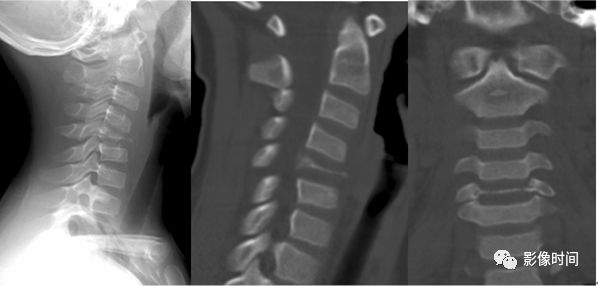

肥胖第 2 颈椎征(the fat C2 sign)

所谓肥胖第 2 颈椎征是指在创伤后摄取的颈椎侧位片上,颈 2 椎体(A)的前后径大于颈 3(B)椎体的前后径。此征象提示累及颈 2 椎体的斜行骨折,而骨折线不一定能在侧位片上显示。

典型病例

外伤后颈椎侧位片(左图)示颈 2 椎体前后径(黑箭)明显大于颈 3 椎体前后径(虚线),呈肥胖第 2 颈椎征;未见明显骨折线。断层摄影(右图)示椎体前部(弯箭)及后部(黑直箭)均可见骨折线。

引用自:1.The fat C2 sign.Radiology 2000;217:359-360.2. Smoker WR.The "fat" C2: a sign of fracture.AJR Am J Roentgenol 1987;148:609-614.